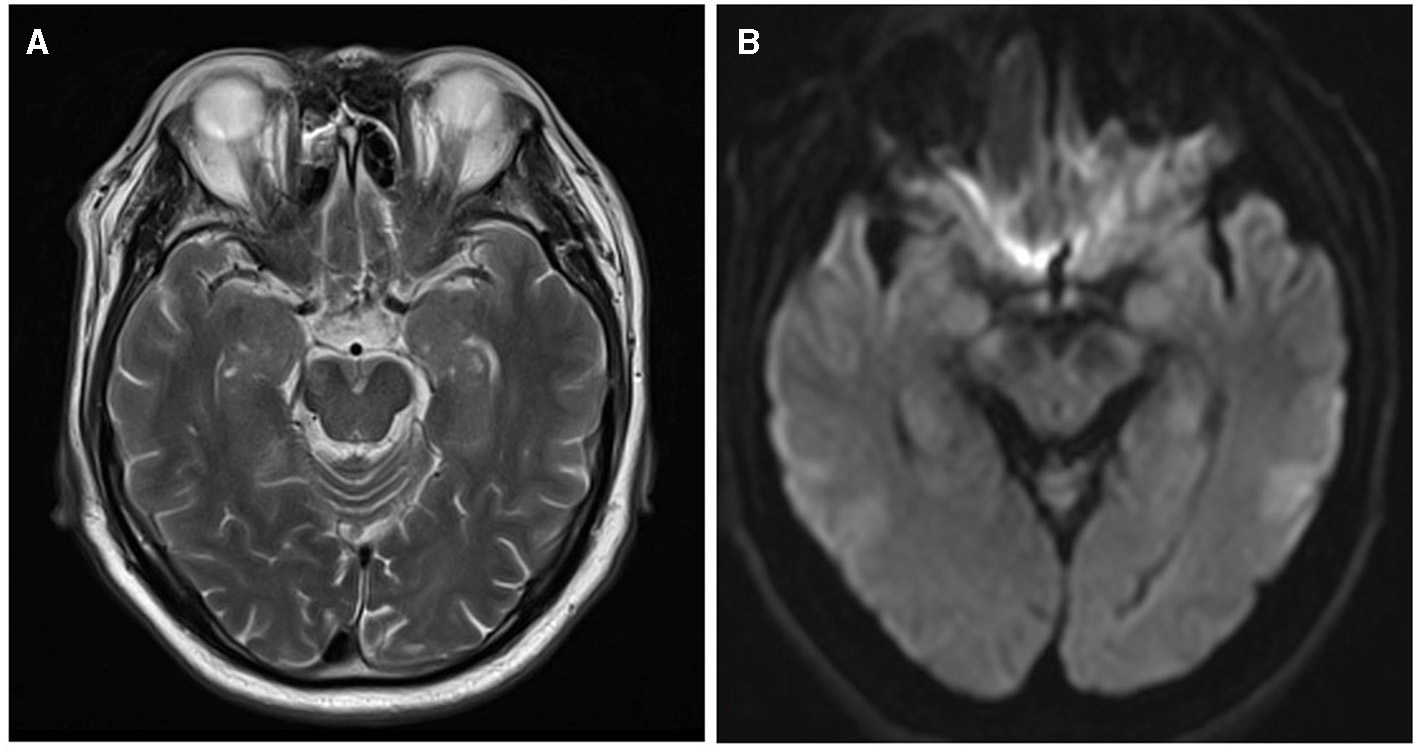

Infarct measurement and location

On the axial DWI sequence, the largest slice of the lesion was selected, and the maximum diameter of the infarct was measured by two physicians separately (5, 17, 18). If there were discrepancies between two observers, they should work together to determine the final measurement. As shown in Figure 2, we found the MCA-M1's normal flow void on T2WI and considered the same layer on DWI as level 0. The next layer near the cephalic side was counted as the first level, and so on (19). Considering the infarction's medial lowest layer as the cutoff point, we defined the distal lesion as the lowest layer of the infarction lesion higher than the cutoff point, and others as the proximal lesions (17, 18, 20).

Figure 2

The layers on T2WI and DWI. (A) MCA-M1's normal flow void on T2WI. (B) The same layer on DWI is considered level 0.